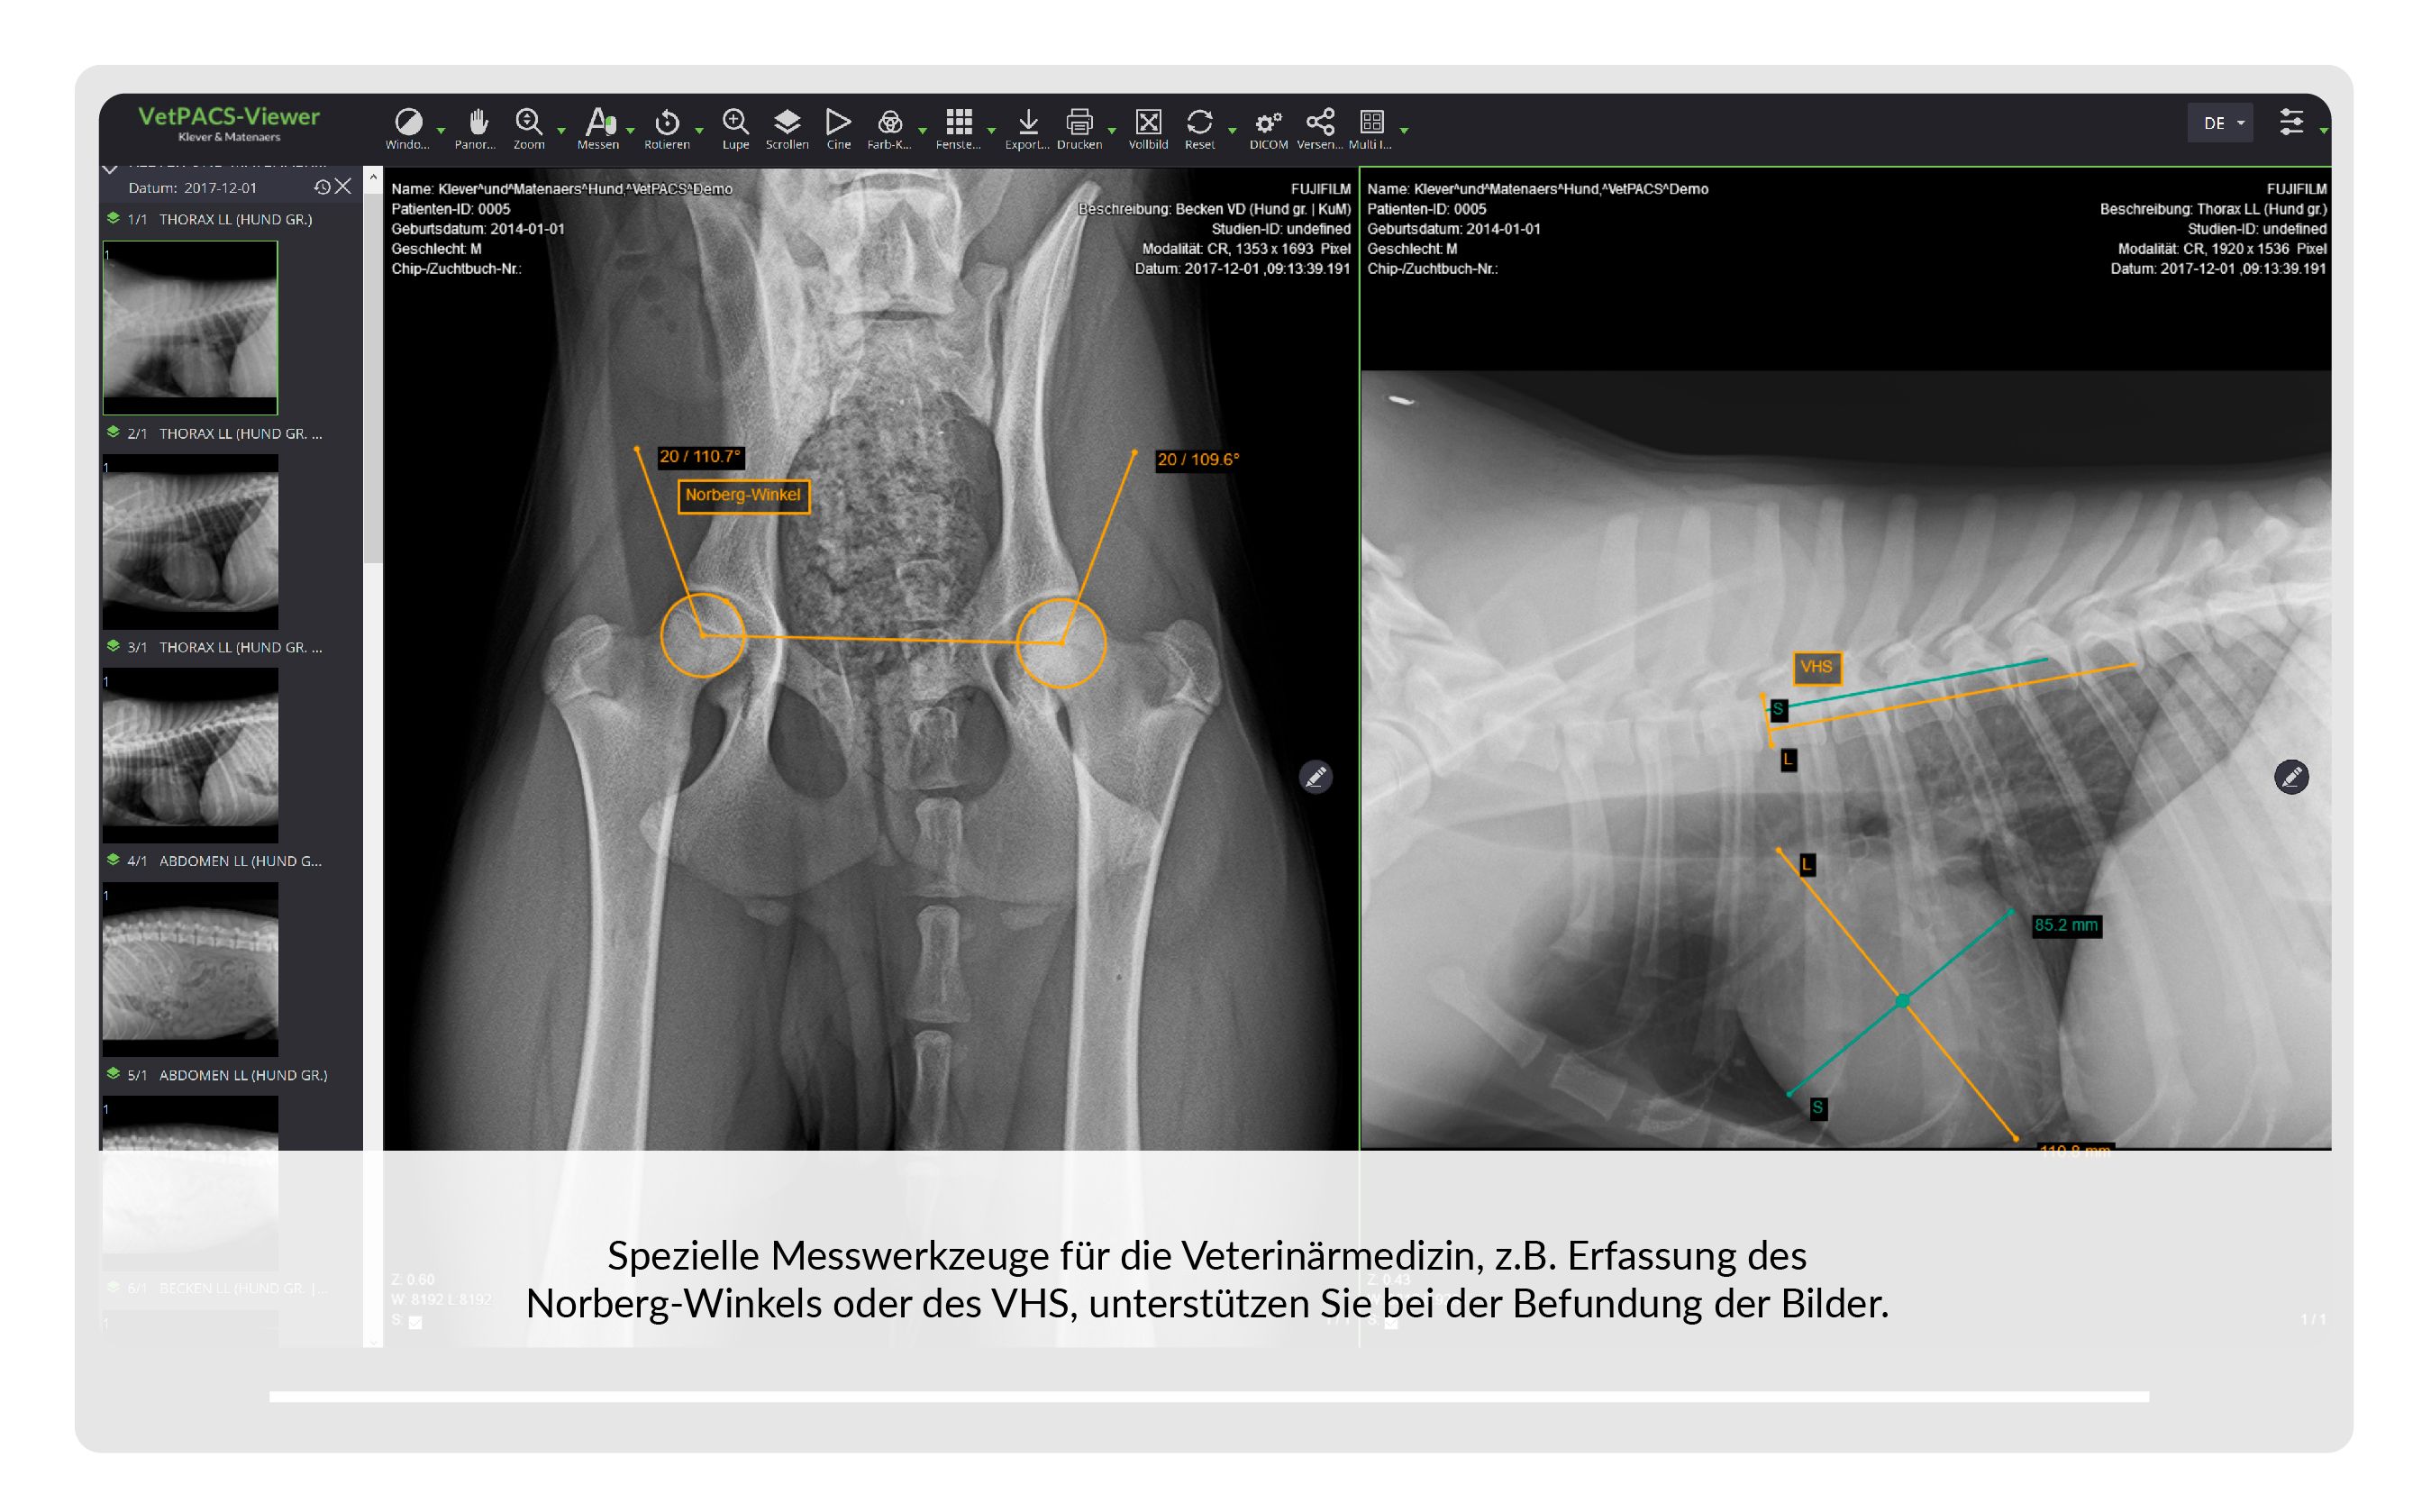

VetPACS

Unsere Lösung zur sicheren Archivierung, Befundung und Kommunikation von medizinischen Bildern und Daten.

| ✓ | Alle Funktionen sind auf veterinär-spezifische Anforderungen optimiert. |

| ✓ | Der integrierte DICOM-Viewer dient zur Betrachtung aller im VetPACS archivierten Daten. |

| ✓ | Volle Unterstützung für Schnitt-bildgebung wie CT/MRT, auf Wunsch mit obliquer MPR und 3D Rendering. |